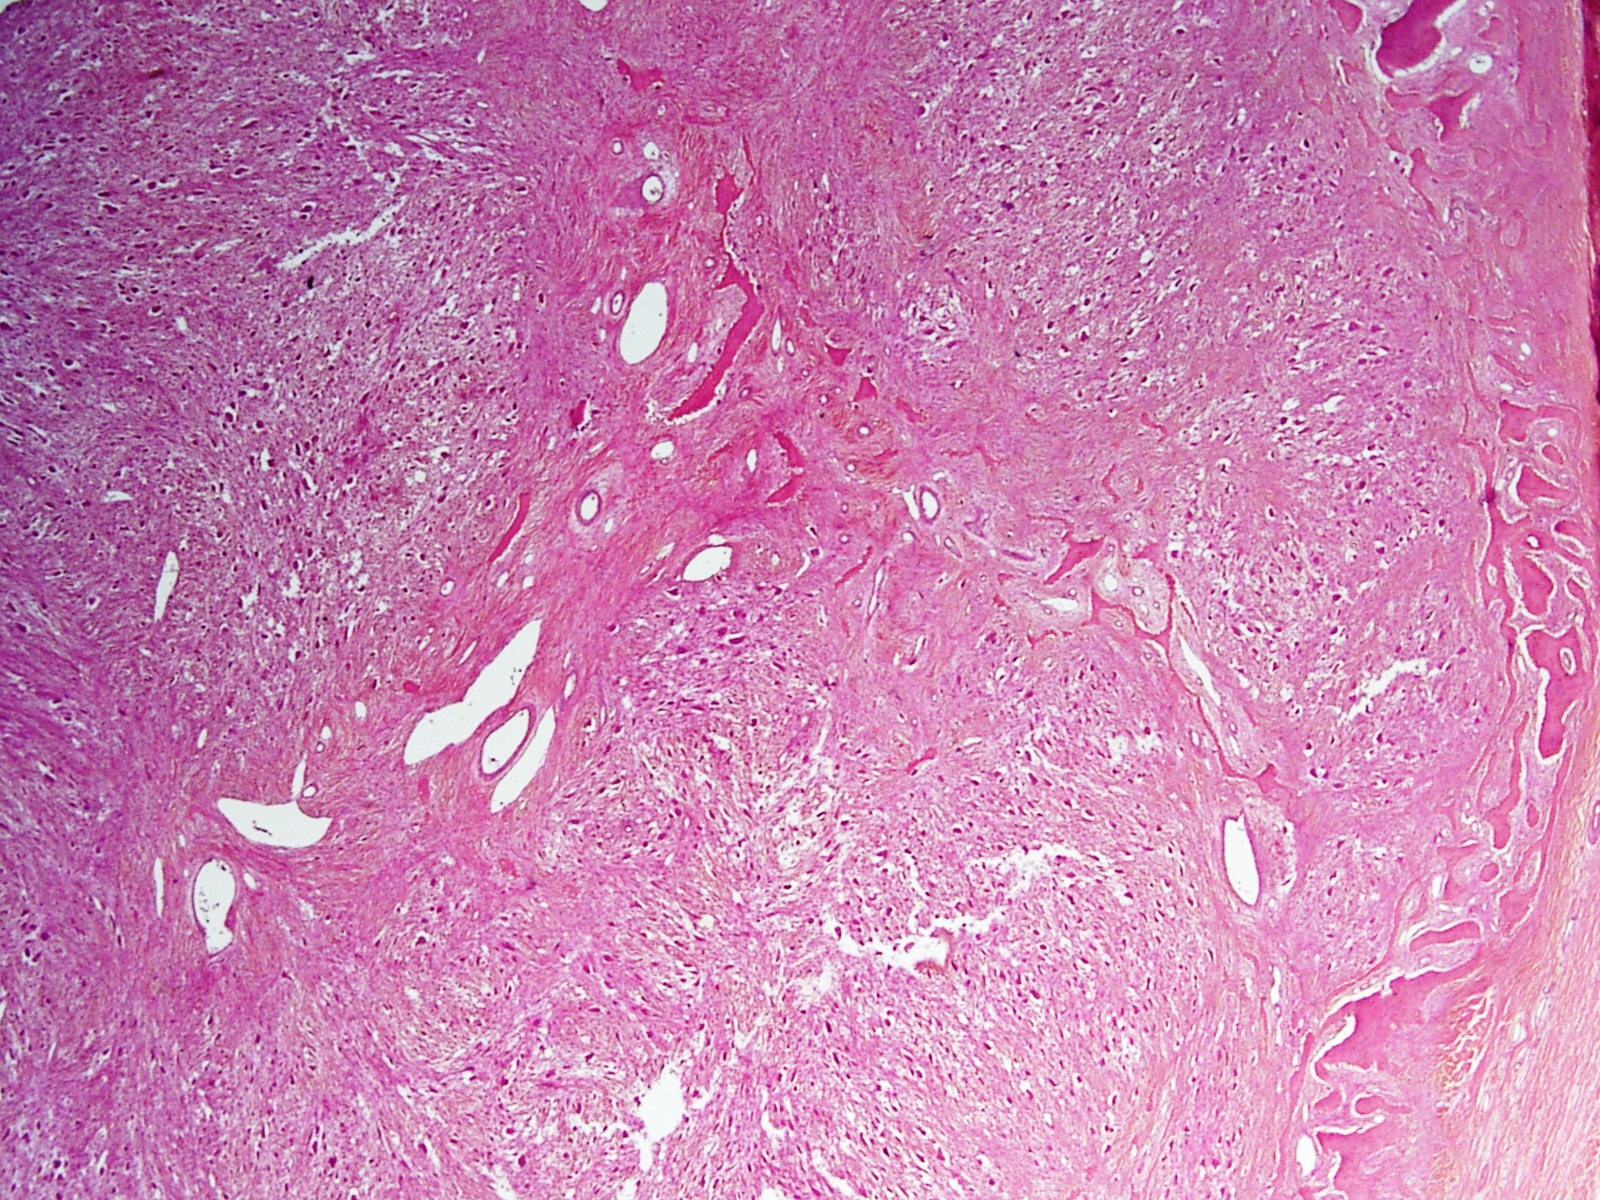

Microscopic (histologic) description

- Lobular pattern composed of groups and clusters of osteoclast-like multinucleated giant cells

- Vascular fibroblastic stroma

- Hemorrhage and hemosiderin deposits

- Tunneling resorption of adjacent uninvolved bone (J Int Oral Health 2015;7:50)

Microscopic (histologic) images

- Giant cell rich lesion (see comment)

- Comment: The lesion is composed of clusters of giant cells in a hemorrhagic fibroblastic stroma. Focal tunneling bone resorption is seen. This feature, along with multiple lytic lesions on radiology, strongly favor brown tumor of hyperparathyroidism. Correlation with clinical history, radiological findings and serum PTH and calcium levels is recommended.

B. Brown tumor of hyperparathyroidism. The photomicrograph shows a lesion composed of bony trabeculae showing resorption along with scattered osteoclast-like giant cells in a vascularized spindled stroma. These microscopic findings with above mentioned clinical and radiological features are characteristic of brown tumor of hyperparathyroidism. Aneurysmal bone cyst affects young adults and shows large blood filled spaces with intervening septae containing fibroblasts and giant cells. Central giant cell granuloma produces radiolucent lesions in children and young women and shows osteoclast-like giant cells near hemorrhagic areas, cellular vascular and fibrous stroma and new bone formation at edge of lesion. Cherubism shows bilateral involvement of mandible and maxilla in young individuals and histology is similar to central giant cell granuloma. Giant cell tumor rarely affects mandible and shows uniform distribution of osteoclast type giant cells among mononuclear cells.